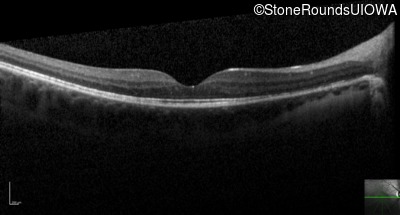

Optical Coherence Tomography - Left - 20/40 +2

Exemplar / OCT Stack